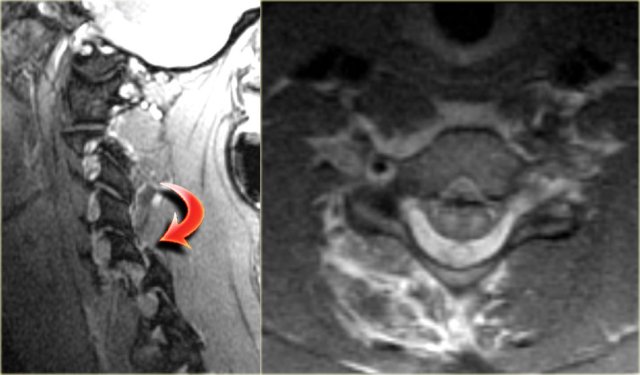

Hyperflexion sprain (3)

The MRI explains the neurological status of this patient.

The MR-findings are:

- Severe soft tissue injury of the posterior paraspinal structures, especially at the C5-6 level, where the interspinous ligament and the ligamentum flavum is ruptured

- Disruption of the C5-6 disc with migration behind C5

- Large amount of spinal cord edema

Continue with the axial image.

The axial image shows the spinal cord injury and in addition to it there is absence of flow void in the right vertebral artery.

This indicates thrombosis as a result of dissection.

In conclusion we can say that this patient had no fracture, but a severe hyperflexion sprain with acute disc herniation, non-hemorrhagic spinal cord injury and vertebral thrombosis.

The MRA confirms the occlusion of the right vertebral artery.